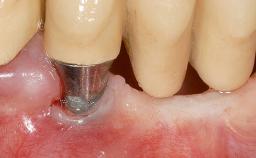

This case demonstrates that a connective-tissue graft in combination with a coronally positioned graft is an effective method of treating cases with peri-implant mucositis and an abutment-level sinus abscess. A 42-year-old man presented with a swelling adjacent to an implant crown at site 21. The swelling had been present for approximately three weeks and was constrained to the buccal and palatal gingival aspects of the implant. A discharge was noted on finger pressure, with localized gingival recession present on the mid- and distolabial aspects of the crown.